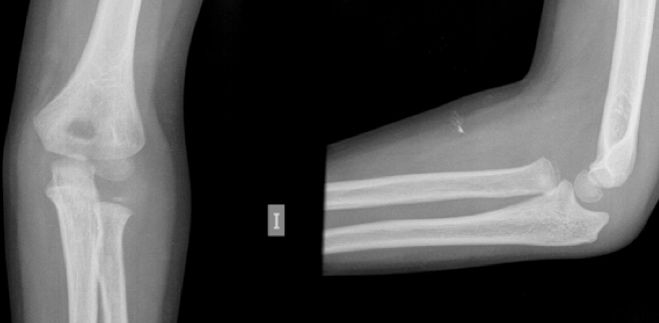

Figura 8: a-d, Imagen radiografica de fractura del cóndilo lateral con desplazamiento articular. Tratamiento quirúrgico mediante reducción abierta y osteosíntesis.